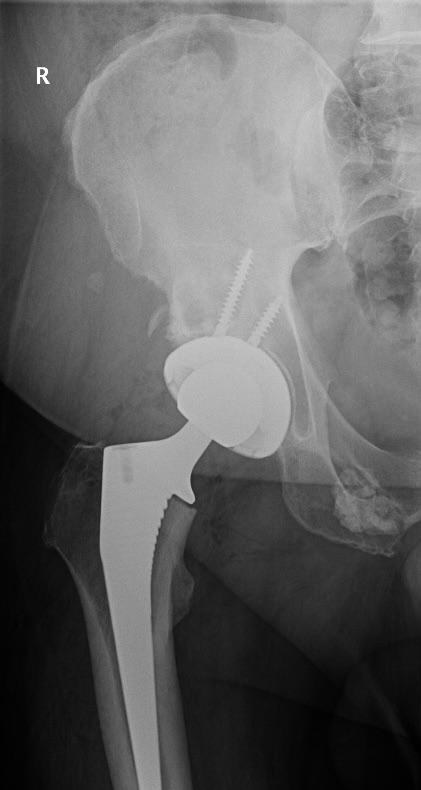

I’m in a situation with this swing an one I don’t want but that’s the way it goes, 18 months ago I had a new hip replacement on the right side, well my left has decided to go haha but it’s going down hill pretty quick were, I’m struggling to walk, sit for long periods of a time, basically like two turtles making it out in the desert Lol got to laugh or I’m in trouble.